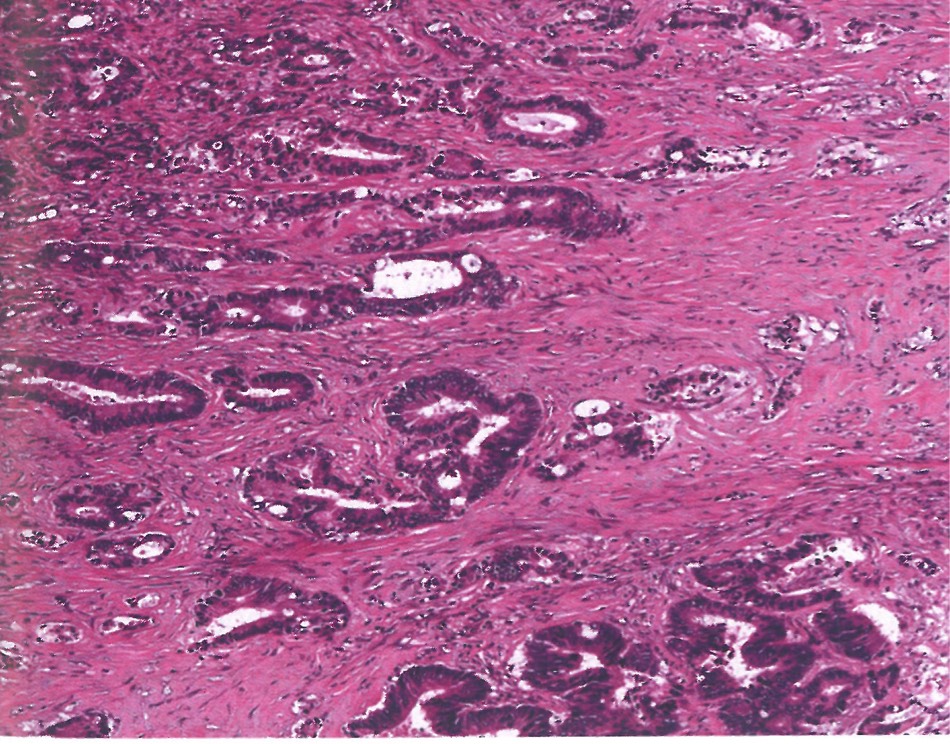

1814. Нозологической единицей, соответствующей данной микроскопической картине рака желудка, считают